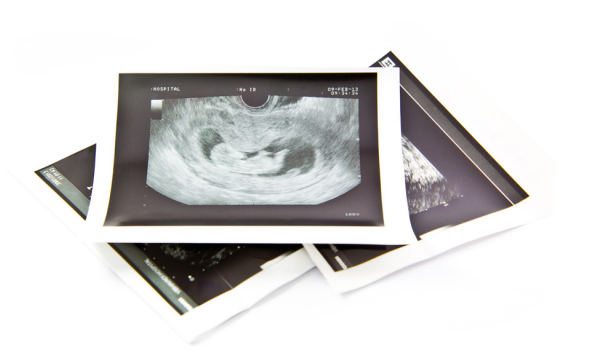

De 12 wekenechografie

Wat betekent de 12 wekenechografie?

De 12 wekenechografie, ook bekend als de termijnecho, is een belangrijk echo tijdens de zwangerschapscontrole. Deze echo vindt plaats tussen de 11e en 14e week van de zwangerschap. Tegen deze tijd is de basisontwikkeling van de baby voltooid en ziet de gynaecoloog: